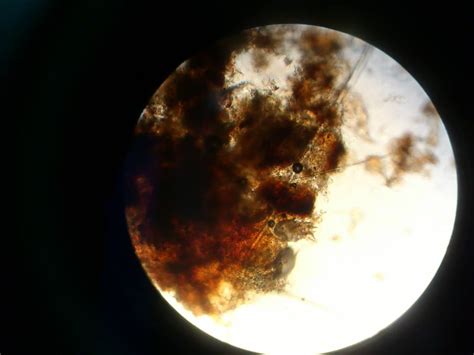

Отодектоз (ушной клещ) собак и кошек

Отодектоз

Отодектоз (ушной клещ)